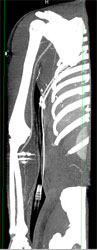

CTA Arm Without Bleed